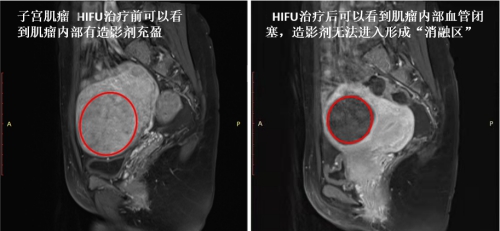

治疗后一个月,复查发现J女士的子宫肌瘤消融率100%(见下图红圈标注区),六个月后子宫肌瘤缩小率50%以上。腹部没有伤口,也未发现明显的毒副作用,在HIFU的精准定位下,病灶部位肌瘤消融,而周围正常子宫肌层和子宫内膜未受损伤,子宫肌瘤得到有效减小,月经也逐渐恢复正常。